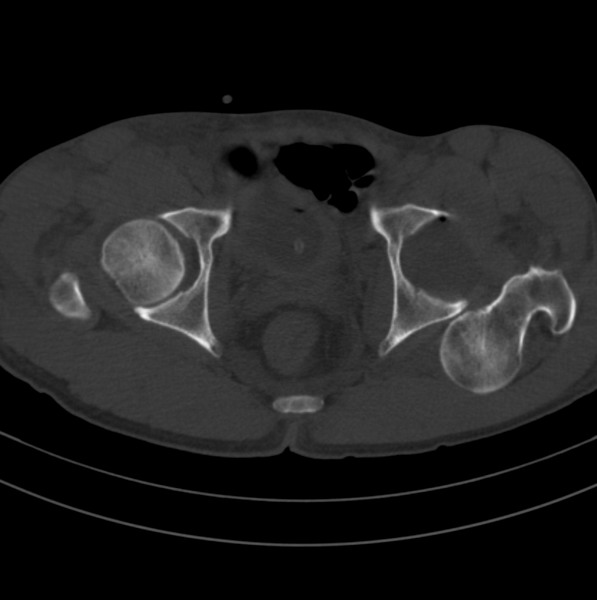

标题: CT18589:股骨头囊状阴影怎么下结论?

男、53

股骨头内的囊状阴影怎么下结论?

一、发病机制

股骨颈疝窝是发生于股骨头基底和股骨颈的一种较少见的良性病变。发病率约在4% 一5% ,好发于中老年人,多无明显症状,常因其他病变检查时偶然发现 。病变多单侧发生,少数为双侧。影像学的正确诊断,可避免不必要的外科手术。

股骨颈疝窝系股骨颈反应区(reaction area)的纤维结缔组织和(或)液体在前部关节囊、髂股韧带及髂腰肌(腱)的机械性压迫下,通过骨皮质疝入松质骨内而形成的窝状骨质缺损 。人体站立或行走时,髋关节囊前方结构处于不断的紧张和松弛交替状态,前部关节囊(尤其是股骨颈轮匝韧带前部环绕区)和相邻的股骨头基底和股骨颈近段前外侧皮质问存在长期的压迫和相互摩擦,使邻近覆盖的滑膜组织可能因受刺激致纤维软骨化生而形成纤维结缔组织和新生软骨,相互摩擦致皮质反应性成骨,后3者成分和其内的液体共同组成了股骨反应区 。

二、影像学表现

x线平片和ct上多表现为位于股骨头基底和股骨颈近段前侧皮质下、股骨颈中轴线外侧的圆形或卵圆形透亮区或软组织密度灶,边界清楚,多伴有薄层硬化缘。病灶最大径线通常<10 mm。病灶或相邻上下层面上相邻皮质大多可见与病灶相连的局限性裂隙样缺损,可作为诊断此病的特异性征象。病灶内通常为纤维结缔组织和(或)液体。内为液体时,病灶呈均匀长t1、长t2信号。纤维结缔组织和液体同时存在时,病灶于t1wi上呈低信号,t2 wi上呈不均匀高信号。